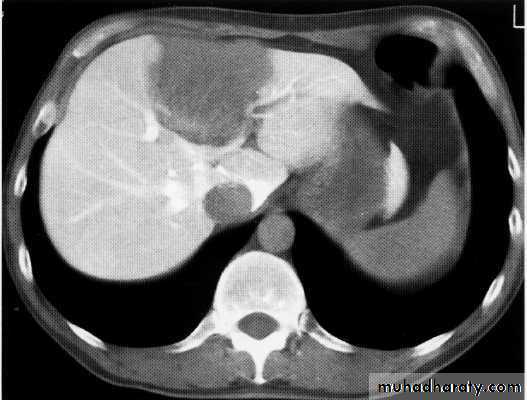

Hepatoma + met.

Met. adenocarcinoma